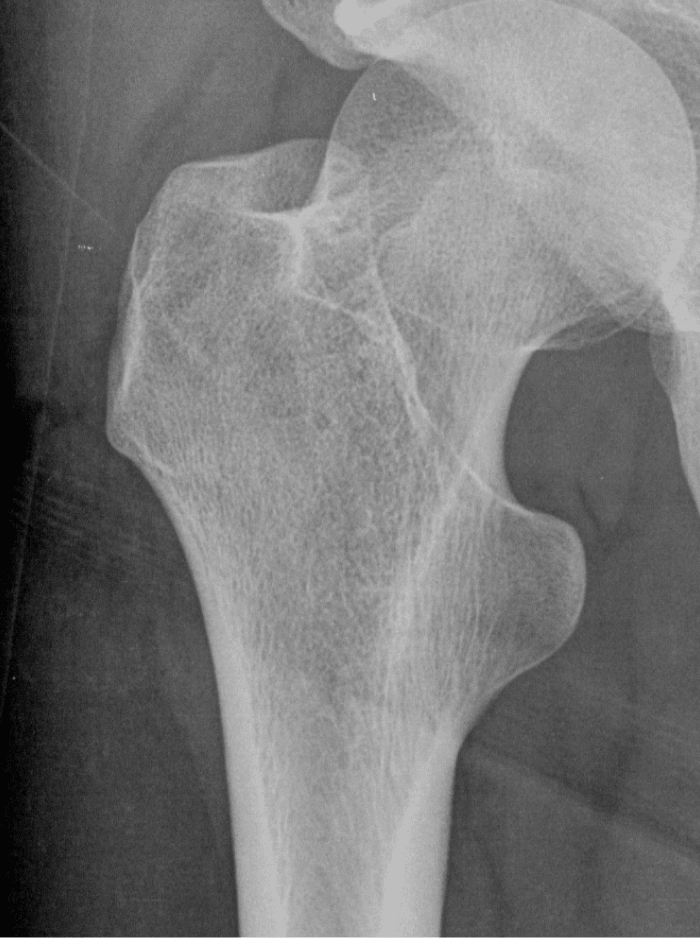

Femur fracture

age 13

Metatarsal fracture

age 16

Tibial fracture

age 57